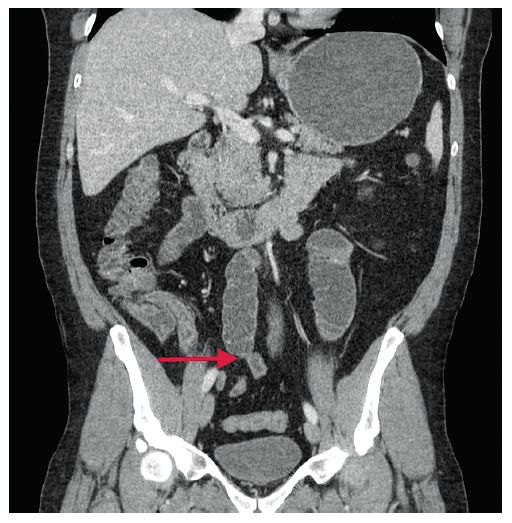

Paciente de sexo masculino de 41 años, con antecedente quirúrgico por trauma abdominal por arma blanca a los 20 años. Ingresa a la unidad de urgencia de nuestro centro por sus propios medios tras presentar un cuadro de dolor abdominal tipo cólico de 6 días de evolución, que se acentuó en las últimas 24 horas, agregándose distensión abdominal y el cese de eliminación de gases y deposiciones. Evaluado por el cirujano CMIBM en la unidad de urgencia, se constata un abdomen distendido, timpánico, sin ruidos hidroaéreos, doloroso a la palpación, sin irritación peritoneal, además de una cicatriz de LMSIU. Se solicita una TAC de abdomen y pelvis, que muestra distensión patológica de asas delgadas con cambio de calibre a nivel del íleon distal y colapso de asas hacia el colon. Se decide la exploración laparoscópica con CLMP, hallándose un segmento de íleon distal adherido a la pared abdominal, determinando la dilatación de asas a proximal hasta 5-6 cm. Se revisa la totalidad del intestino delgado y el colon, sin encontrarse otras lesiones. No existe compromiso vascular del intestino. El paciente evoluciona con íleo postoperatorio (Clavien Dindo II), con buena respuesta al tratamiento médico mediante proquinéticos y sonda nasogástrica por 24 horas. A las 48 horas post cirugía el paciente comenzó con dieta líquida con buena tolerancia. Se decide el alta al quinto día de la cirugía. Los controles alejados al mes, 3 y 6 meses del postoperatorio mostraron buena evolución, sin síntomas.